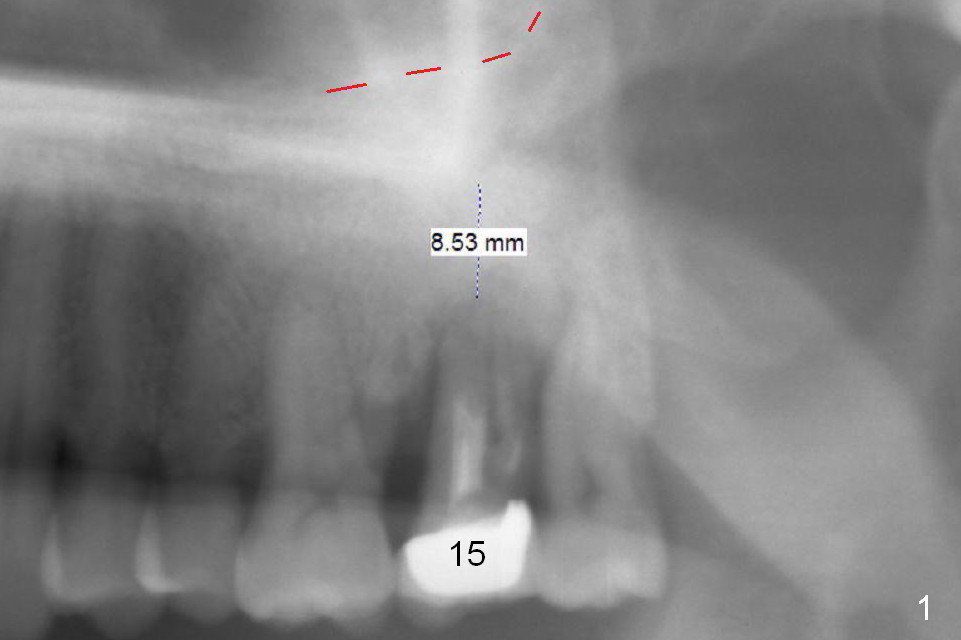

When the tooth #15 is extracted, the buccal plate is found to have been lost. The depth of osteotomy in the native bone is 8.5 mm (Fig.1,2). When a 5.5x15 mm implant is placed (Fig.3), the insertion torque is > 55 Ncm. The implant is palatally placed with a 10x10 mm Osteogen plug being placed in the deep portion of the buccal gap for buccal plate repair (Fig.4 *). The superficial portion of the remaining socket is filled with .5-1.5 mm allograft/autogenous bone/Osteogen (Fig.5 *). The drawback of this procedure is that the abutment is placed prior to placement of the graft. The latter fails to reach the deepest area of the defect. If periimplantitis develops because of insufficient graft, do it again in due time.